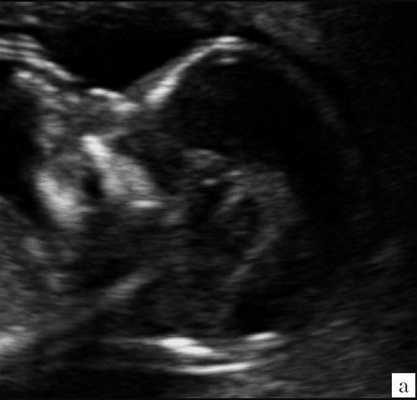

Ультразвуковая анатомия среднесагиттального скана головного мозга плода

Одним из критериев среднесагиттального корректного скана головного мозга плода в срок 11-14 недель беременности является отсутствие визуализации сосудистого сплетения и скуловой кости верхней челюсти, наличие визуализации кости носа и небного отростка верхней челюсти (рис. 1). Обязательным является наличие на скане диэнцефалона-таламуса (Thalamus), который продолжается в ствол мозга (brain stem), а также чуть ниже в средний мозг (midbrain), с продолжением в интракраниальное пространство, представляющее собой IV желудочек мозга, в котором можно визуализировать гиперэхогенное сосудистое сплетение. Между стенкой IV желудочка и затылочной костью видна анэхогенная большая цистерна головного мозга (cisterna magna). Между затылочной костью и кожей визуализируется воротниковое пространство. Для полноценной оценки структур среднего и заднего мозга необходимо оценить их наличие, размер, взаимоотношение, так как при патологии головного мозга и позвоночника эти критерии меняются.

Рис. 1. Ультразвуковая соноэмбриология структур головного мозга в среднесагиттальном скане в 13 недель беременности.

1 - диэнцефалон;

2 - средний мозг;

3 - ствол мозга;

4 - интракраниальное пространство, или IV желудочек;

5 - большая цистерна;

6 - воротниковое пространство.

Особенностями визуализации этих структур является их гипо/анэхогенность. Так, при сроках 11-14 недель беременности таламус, ствол мозга, средний мозг выглядят практически анэхогенными. Итак, нормальная ультразвуковая анатомия этих структур головного мозга плода имеет следующие особенности: ствол и IV желудочек выглядят как анэхогенные продолговатые структуры, имеющие непосредственную близость (как бы выходящие) из диэнцефалона и среднего мозга. Все выше перечисленные анатомические структуры могут быть измерены и должно быть оценено их взаиморасположение (рис. 2, а).